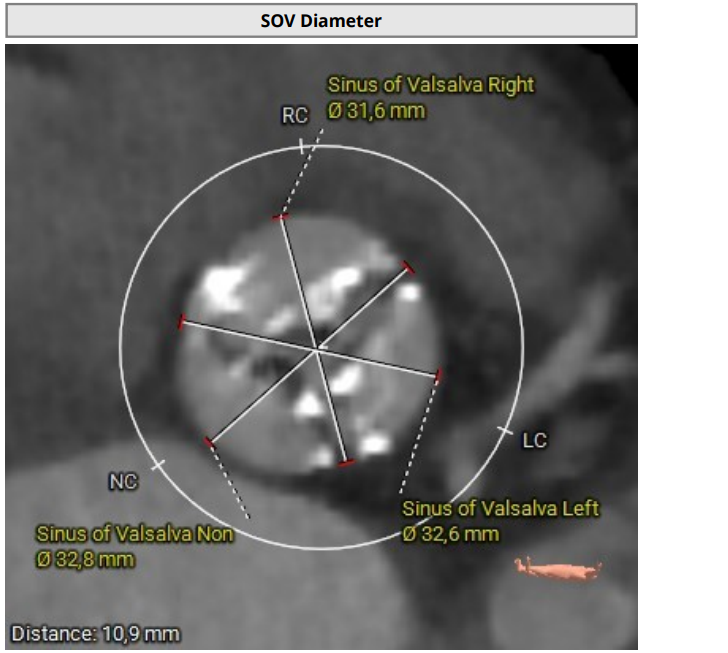

Since 2023 - frequent hospitalizations due to attacks of chest pain, attacks of nocturnal asthma. According to echocardiography - EF-52%. AV leaflet opening 0.5 cm. Prominent calcification of the aortic valve and fibrous ring. V-5.9 m/s, PGmax-140 mmHg, PGmean-88 mmHg, S-0,5 cm2. Aortic regurgitation grade II. Mitral regurgitation grade II-III. No zones of local contractility disturbance. Consulted with a cardiac surgeon, surgical correction of aortic defect was recommended.

The rightsubclavian vein was punctured. A 6F intraducer was inserted. The endocardialelectrode for temporary cardiac stimulation was placed in the right ventricularcavity. The left radial artery was punctured. A 6F intraducer was placed, andan invasive pressure line was connected. The left common femoral artery waspunctured. The 6F intraducer is inserted. Pigtail 6 F diagnostic catheter isinserted into the non-coronary sinus. Puncture of the right common femoralartery was performed. Two intravascular sutures were placed using the Pro Glidepre-stitching technique. The 12F intraducer was placed in the lumen of the rightfemoral artery. The Confida wire wasguided into the left ventricular cavity. Aortic valve valvuloplasty wasperformed using balloon catheters 20.0-40.0 mm, 25.0-40.0 mm. Asystole wasregistered on ECG and resuscitative measures were started. During indirectheart massage, endovascular prosthesis Portico - 29mm was implanted in aorticposition. At the control aortography, the aortic valve prosthesis is optimallyspread out.